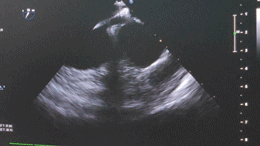

鑒于患者聲窗條件不佳,靜息狀態下經胸超聲難以明確卵圓孔未閉的具體情況,為確保手術操作的精準性與安全性,故擬行單純經食道超聲引導下經股靜脈介入封堵術。

本例患者靜息狀態下PFO隧道長度7.96mm,開口0.85mm,故選用D-shufo 1824-3封堵器,配套9F封堵器介入輸送系統,完成手術封堵。